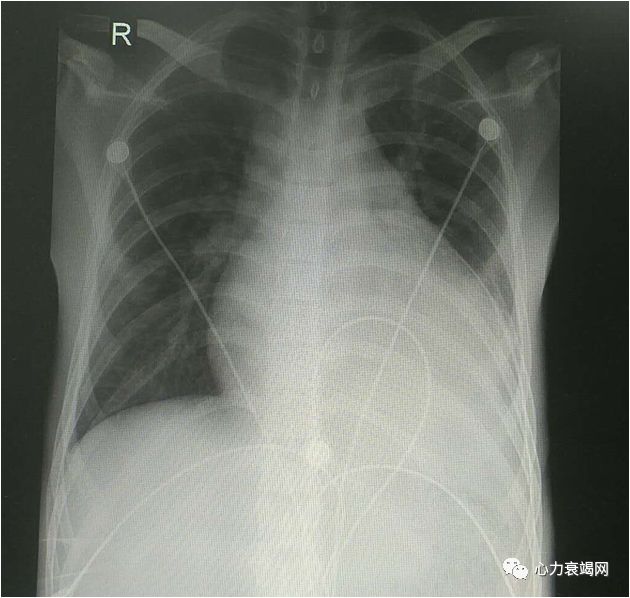

► 患者:唐某,男,21岁

► 主诉:胸闷气促2月,加重伴双下肢浮肿半月

► 现病史:患者2月前感冒后逐渐出现胸闷气短,自行在社区医院输液治疗后症状缓解不明显,此后患者未行继续治疗,胸闷气短仍间断出现,伴咳嗽咳痰。半月前胸闷气短症状加重,伴乏力,并逐渐出现双下肢及颜面部水肿,夜间睡眠需高枕,遂来我院就诊。起病以来,精神欠佳,睡眠一般,食欲下降,二便正常,体重明显增加

► Bp 100/70mmHg,R 25次/分,P 100次/分,T 36.0 ℃

► 神清,营养良好,双眼浮肿,全身皮肤巩膜无黄染,颈软,颈静脉怒张;双肺呼吸音粗,可闻及湿啰音;心界向左下扩大,HR 100次/分,律齐,心尖部可闻及3/6级收缩期吹风样杂音;腹软,肝脾肋下未及,双肾区无叩击痛,移动性浊音阴性;双下肢中度凹陷性水肿